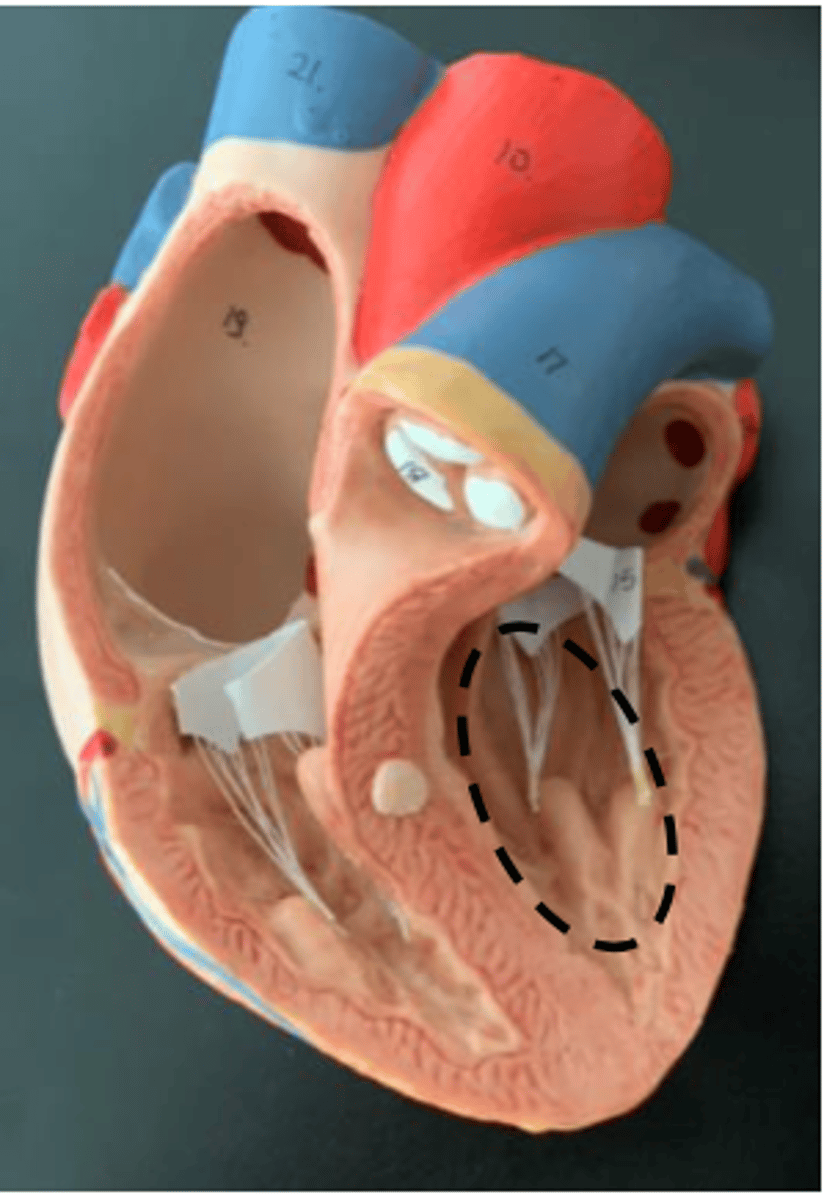

papillary muscle

muscle that attaches to the chordae tendineae

<p>muscle that attaches to the chordae tendineae</p>

chordae tendineae

the little strings below the tricuspid and bicuspid valve

<p>the little strings below the tricuspid and bicuspid valve</p>

trabeculae carneae

surface on the inside ventricle walls (Freddy Krueger skin)

<p>surface on the inside ventricle walls (Freddy Krueger skin)</p>